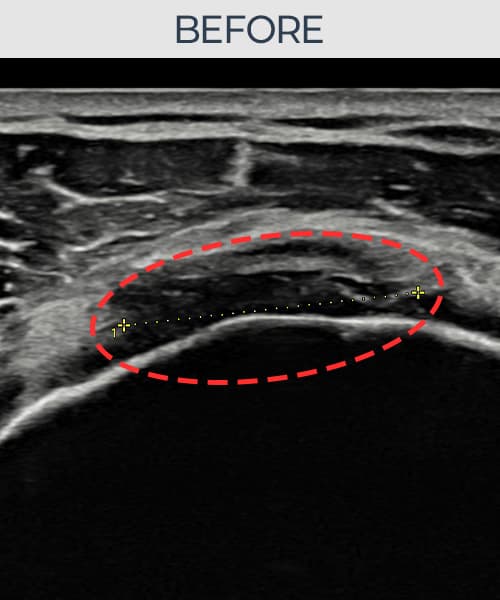

右侧 冈上肌腱 石灰化肌腱炎

13mm × 9mm